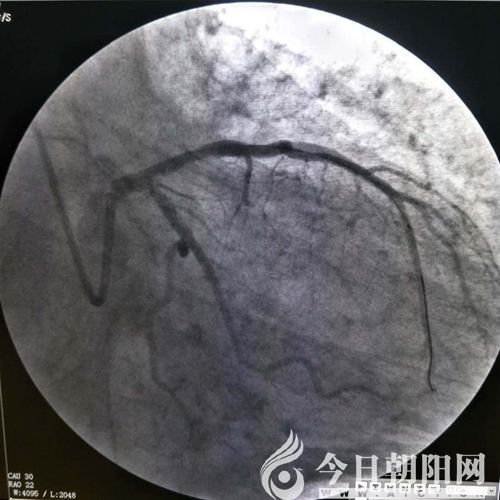

鄭某術(shù)前

兩名患者均屬于危急情況,相比之下,患者鄭某更重一些。單爽立即為鄭某實施手術(shù),術(shù)中見冠脈前降支支架內(nèi)100%狹窄,回旋支80%狹窄,血管內(nèi)布滿新發(fā)血栓,操作難度非常大。在導(dǎo)絲和球囊艱難通過后,依次進(jìn)行預(yù)擴(kuò)球囊及后擴(kuò)球囊于支架內(nèi)擴(kuò)張,前降支恢復(fù)三級血流,患者癥狀立即緩解。由于120急救中心在接診患者過程中,及時予以診斷,并開通綠色通道、免費心梗“一包藥”口服、建立左手靜脈通路等及時正確的處置,為患者的救治贏得了時間。